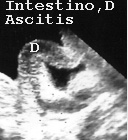

Las asas intestinales son muy visibles cuando hay ascitis o líquido dentro. En la (Fig 45A y 45B) se ve intestino delgado normal.